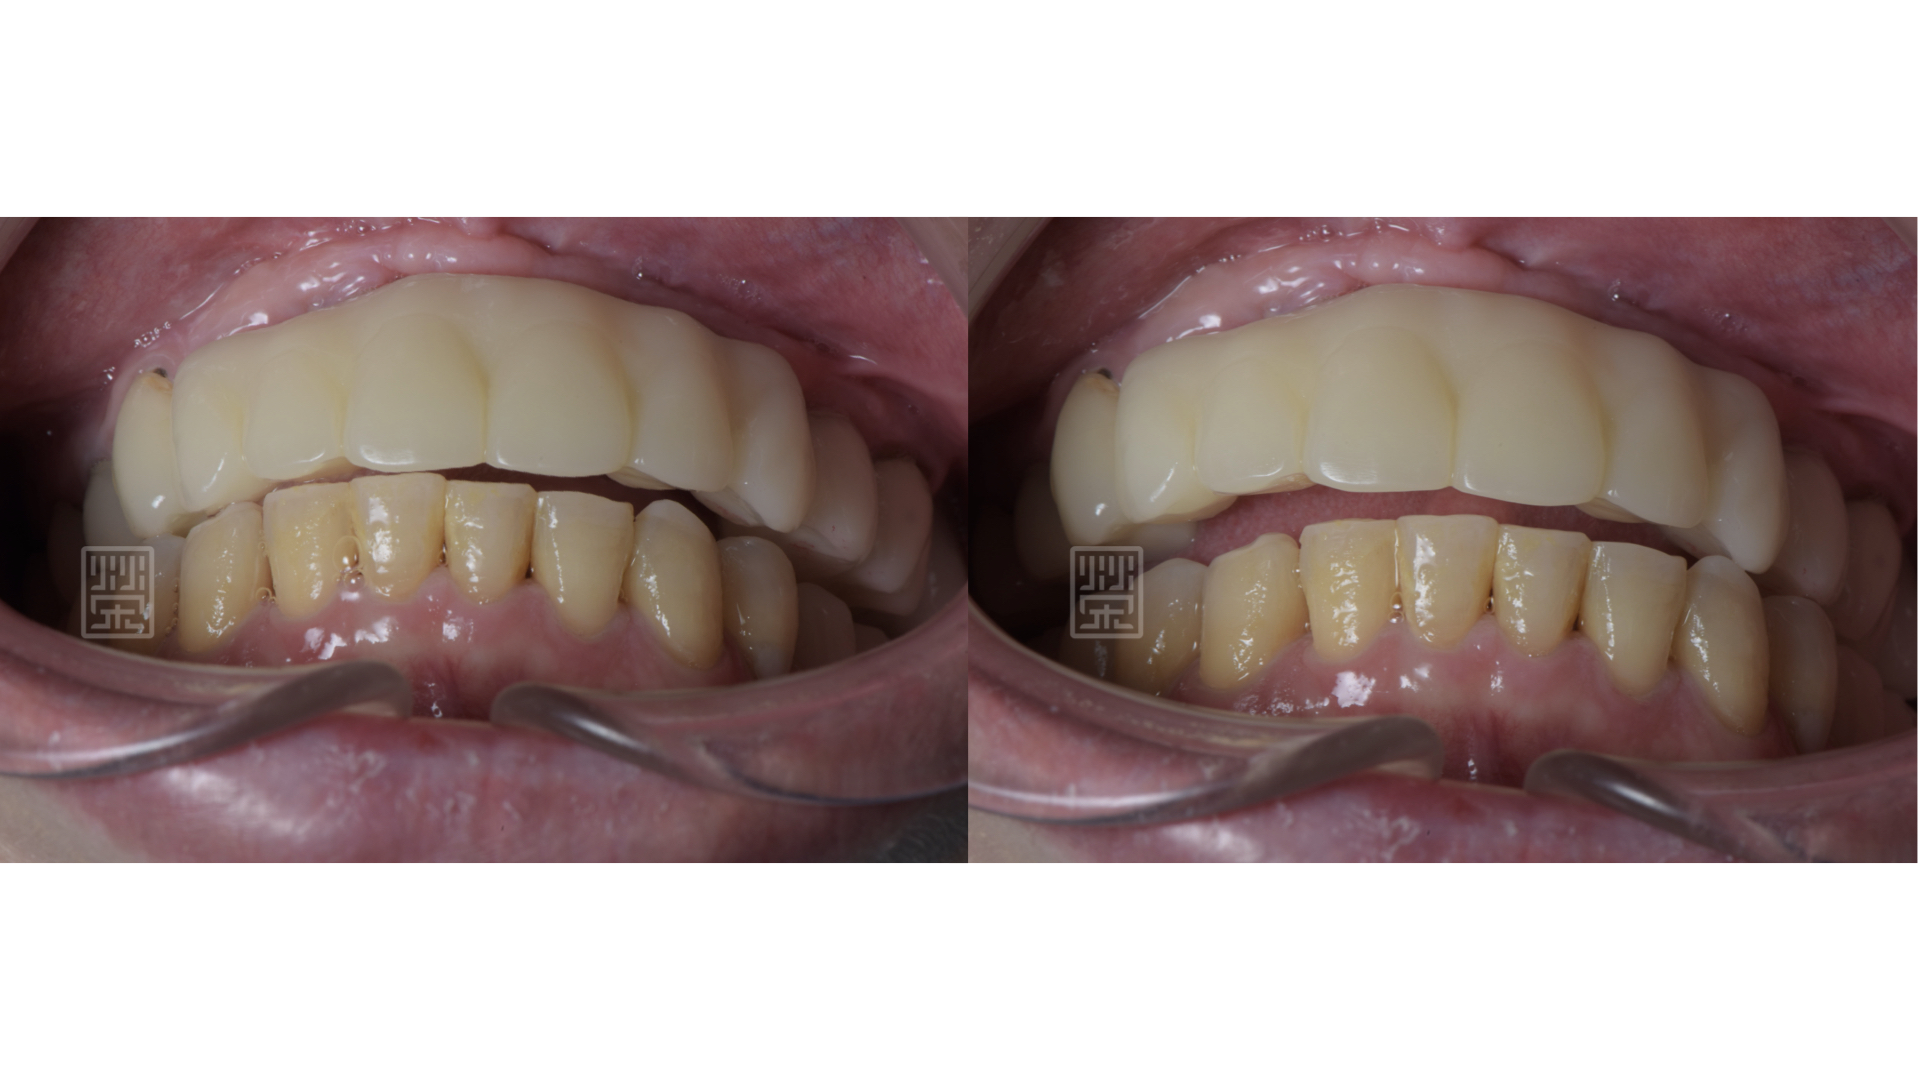

藉由臨時假牙、矯正、更新臨時假牙,讓型態、長度、唇形充分瞭解與溝通

矯正後,再將門牙拉長,達到理想的牙齒的長度